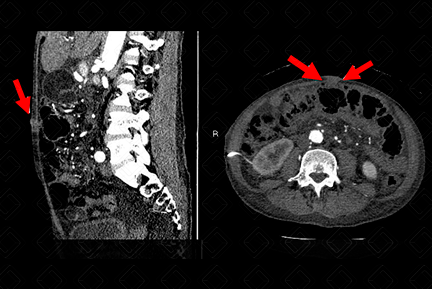

Texto alternativo para a imagem Créditos: Dra. Elazir Mota - Rio de Janeiro/RJ

Descrição da figura: Tomografia computadorizada do abdome evidenciando nódulo, com densidade de partes moles na região umbilical - setas vermelhas (paciente em reestadiamento de CA de cólon).

• Nódulo da irmã Maria José pode ser observado na ultrassonografia ou tomografia computadorizada ou ressonância magnética do abdome como lesão nodular, com densidade de partes moles, usualmente captante do contraste. Na ressonância magnética do abdome, podemos observar restrição a difusão.